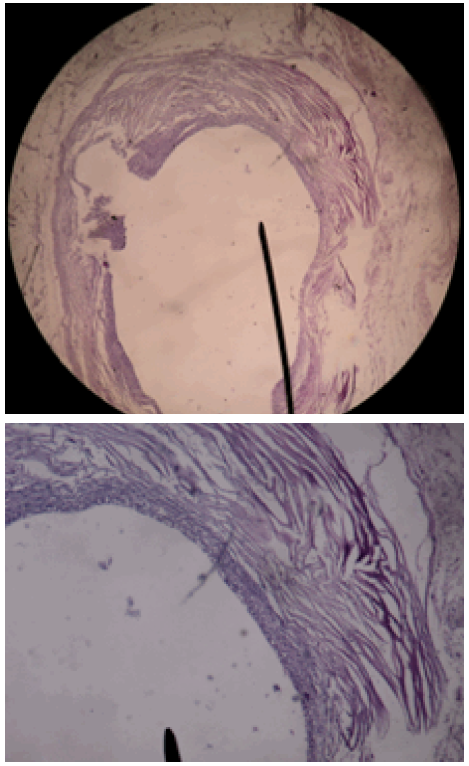

Tinción hematoxilina-eosina.

Figura 5: Tinción hematoxilina-eosina.

Fuente: Documento obtenido durante la realización del estudio.

En la Figura 4 se evidencia fragmento de tejido de 5x4x11cm con losange de piel de 4x1.5cm y superficie irregular compuesta por tejido adiposo; al corte a 0.8cm la piel presenta formación nodular de color pardo amarillento de 1.5x1.8cm con formación quística de 0.6cm de diámetro bien delimitado por tejido fibroso. También se evidencian tres formaciones quísticas de 0.3-0.8cm a 4 y 8cm debajo de la piel y paredes de 0.1cm de espesor con contenido seroso; se incluyen seis cortes.

La Figura 5 corresponde a una paniculitis mixta sin vasculitis con reacción granulomatosa focal y fibrosis reactiva circundante; formaciones quísticas en tejido celular subcutáneo de paredes fibrosas, recubiertas en su cara interna por macrófagos y células epitelioides a cuerpo extraño. Estos hallazgos son compatible con cisticercosis subcutánea.